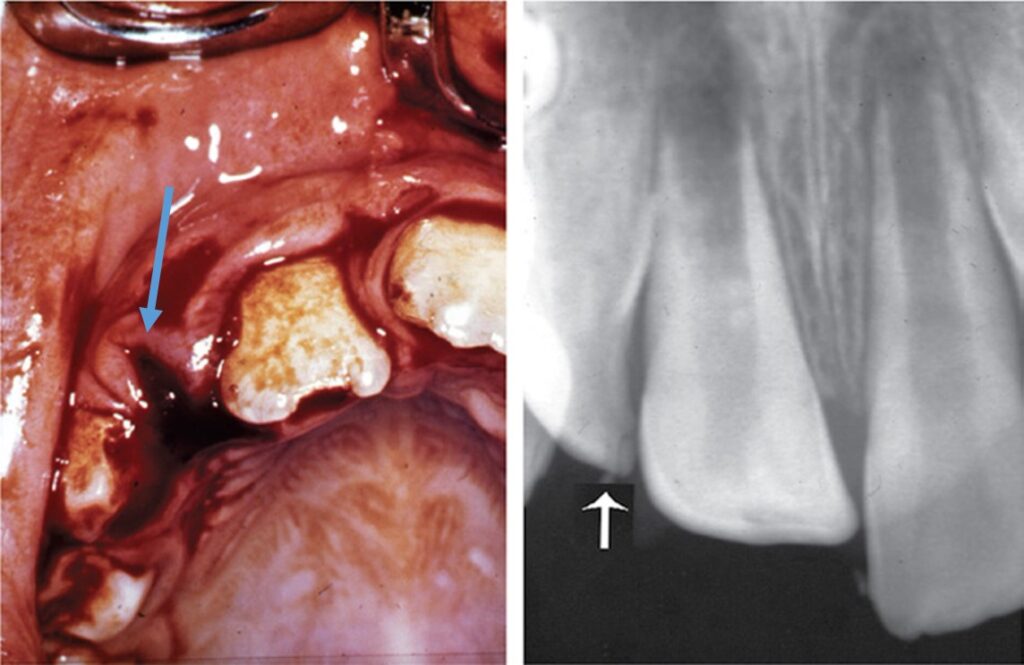

Thực tế xoang tủy thường lớn hơn và khoảng cách từ sừng tủy đến rìa cắn thường nhỏ hơn khoảng cách quan sát thấy trên X quang. Trong một số ít trường hợp, sự dịch chuyển của răng sữa có thể dẫn đến gãy mầm răng vĩnh viễn, dấu hiệu này có thể được thể hiện trên phim X quang.

Nứt men có thể nhìn thấy dưới dạng các đường sẫm màu chạy song song với các thanh men và kết thúc ở tiếp nối men-ngà (Hình 13.8).